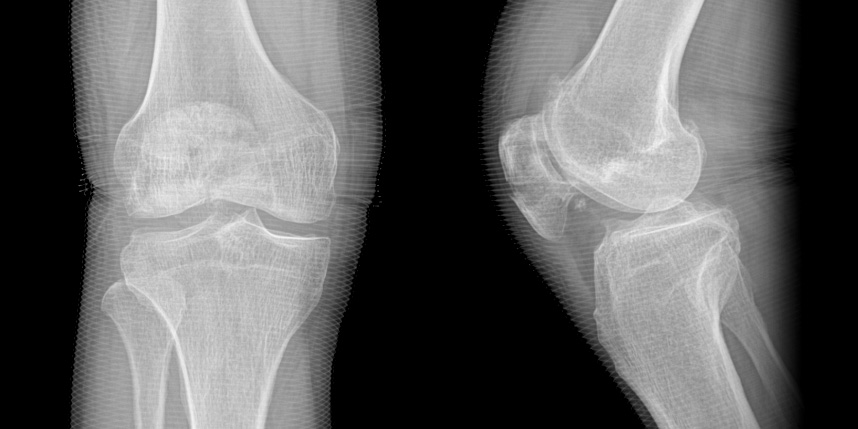

무릎 골절